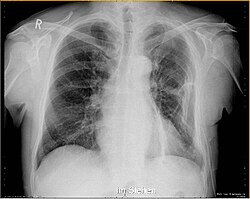

Sumnja na prijelom rebara najpouzdanije se potvrđuje;

- radiografijom prsnoga koša u nekoliko pravaca,

- ultrazvučnim pregledom

- kompjuteriziranom tomografijom.

Dijagnostika prijeloma rebra nije uvijek laka, kao i dijagnostika komplikacija ovih prijeloma koji moraju pravodobno biti uočeni jer mogu životno ugroziti povrijeđenog zbog; krvarenja, ozljeda srčane i plućne maramice, pluća i organa trbuha.

Također radiološkim dijagnostikom treba isključiti i moguće druge ozljede koje mogu biti udružene sa prijelomom rebara.